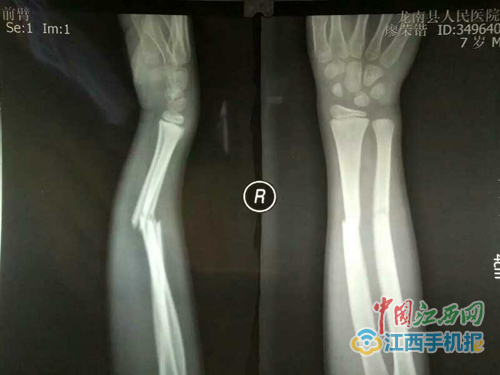

廖荣锴右手桡尺骨骨折的Ⅹ光片子

中国江西网讯 龙南县7岁男童廖荣锴因不慎跌倒致右手臂桡尺骨两根骨头骨折并错位,经医院检查后,热心的医师建议开刀做手术上钢板治疗。但全家考虑到廖荣锴年仅7岁,不忍心承受刀割手术的痛苦及承担未测的风险,家人一时间一筹莫展。

经过几个小时的奔波,很快就来到蓝飞医师处。蓝飞经过细致地检查,查问伤情,认真地看了廖荣锴骨折的片子后,马上制定了治疗方案,现场进行了中医手法复位及外敷特制的消肿止痛、抗菌消炎、活血化瘀、续筋接骨药物。由于廖荣锴的父母对蓝飞高度的信任,由龙南至赣州蓝飞处三天一次的往返复诊密切配合换药治疗。

经过两周的用药,廖荣锴的伤手大有好转,肿胀消退,疼痛消失,手也能稍动握拳。继续用药数周后,手已能写字、做上举等功能锻炼。通过蓝飞近两个月的精心治疗,乖巧听话的小荣锴重返学校,恢复了从前的学习和玩耍。现在的廖荣锴已完全康复,全家对蓝飞(蓝师锡)医师万分地感谢。赣州骨伤科健康热线:蓝飞13907970648。